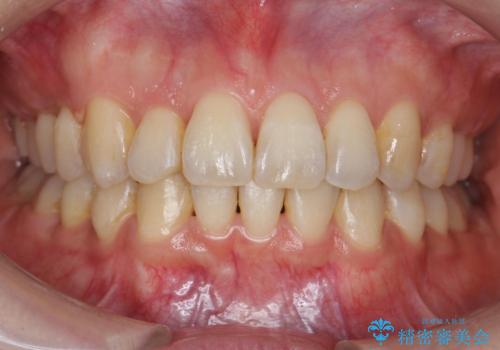

【モニター】八重歯と前歯のクロスバイト ワイヤーを併用しインビザラインで矯正治療